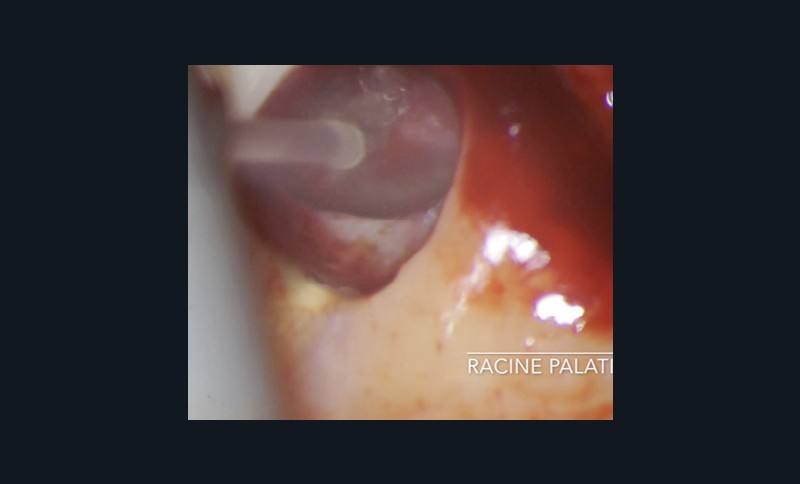

Si les isthmes sont particulièrement mis en évidence au niveau des molaires mandibulaires, cela devient médicalement important au niveau des molaires maxillaires.

La diffusion bactérienne et de leurs toxines, au niveau des molaires maxillaires est à l’origine d’un grand nombre de sinusites maxillaires chroniques, d’origine dentaire. Celles-ci sont principalement causées par l’absence de traitement du deuxième canal MV, qui existe dans 90 % des cas, et il est à noter que ces deux canaux – MV1 et MV2 – sont également reliés par un isthme.

Le nettoyage des isthmes intercanalaires reste un réel problème, et semble responsable de nombreux échecs [43]. Par ailleurs, il est nécessaire d’utiliser des instruments qui évitent de propulser les débris, tant apicalement que latéralement, en obturant les entrées isthmiques avec des débris compactés.

L’utilisation d’instruments en nickel titane, tels que le XP Shaper (FKG), le Vortex blue (Dentsply) ou le Profile (Dentsply), optimise la remontée des débris et s’inscrit dans cette nouvelle philosophie. En conséquence, la combinaison XP Shaper, XP Finisher et l’irrigation avec l’Er:YAG semblent optimiser nos traitements [44,45].

Le passage du laser est répété plusieurs fois, en début, au milieu et en fin de préparation. Un protocole peut alors être proposé : 40 mJ ; 20 Hz (fig. 7). L’utilisation de biocéramiques Bioroot (Septodont) ou Total Fill R (FKG) permet de sceller le système ainsi nettoyé, en assurant une action biologique de longue durée [46] (fig. 8a à c).